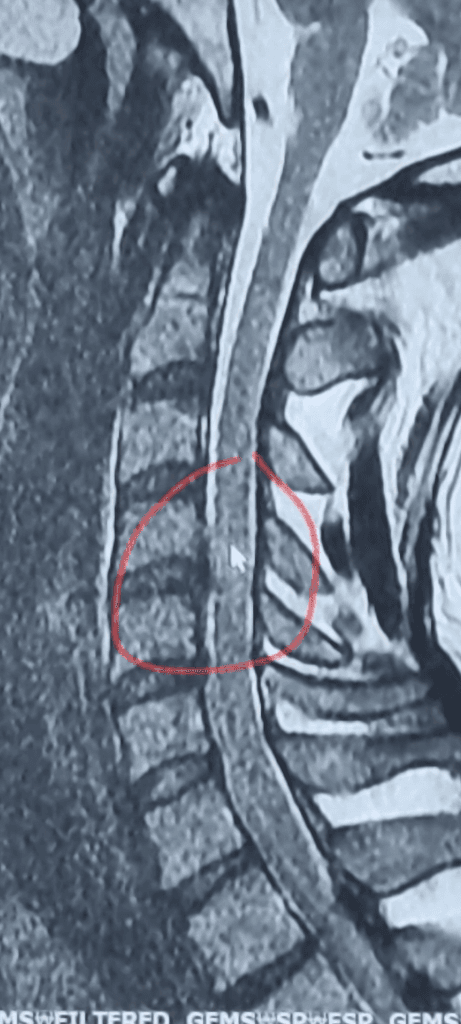

2.괜찮아보인다고 판단했던 mri

저런식으로 사진을 찍어 올린 걸로는 정확한 판독이 되지는 않으나, 올려주신 사진만으로는 탈출증이 심각하게 있어보이진 않습니다. 신경관은 세번째 사진에서 판단할수 없습니다.